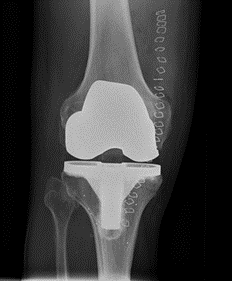

Fakta om en knæledsprotese

En knæledsprotese består af 3 dele:

- Protesedelen på lårbenet består af rustfrit stål.

- Protesedelen på skinnebenet er af rustfrit stål eller titanium og består af en metalplade med køl, som går ned i marvhulen på skinnebenet. Oven på metalpladen sidder hård plastik, som danner led med protesedelen på lårbenet.

- Protesedelen på knæskallen er af plastik.

Protesedelene kan gøres fast til knoglerne med knoglecement, der binder som lim eller uden knoglecement, hvor protesen har en overflade som knoglen vokser ind i.

Knoglecementen, som vi anvender, er af et fabrikat, som har været anvendt i mere end 30 år uden problemer.